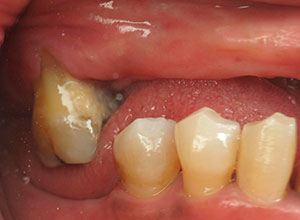

Se utiliza en pacientes completamente edéntulos, es decir, que no tienen ninguna pieza dental, ya sea en el maxilar, en la mandíbula o, incluso, en ambos. Y, que, además, presentan una pérdida moderada de hueso.

Por otro lado, este tipo de rehabilitación también está indicada en aquellas personas que, aunque aún mantienen dientes en la boca, dichas piezas dentales presentan un pronóstico imposible a corto plazo y están abocados al edentulismo total.

Antes de comenzar a fabricar la prótesis es necesario realizar un completo estudio del caso concreto de cada paciente, para asegurarnos de que ésta se ajusta completamente a sus necesidades (en todo lo relativo a color, tamaño, comodidad, etc).

Este procedimiento requiere, en primer lugar, que tomemos los registros de la boca del paciente a través de una tomografía cone beam la cual se transfiere a el software que se encarga de proyectar la prótesis a través de la reproducción digital en 3D y obtener el mejor diagnóstico.